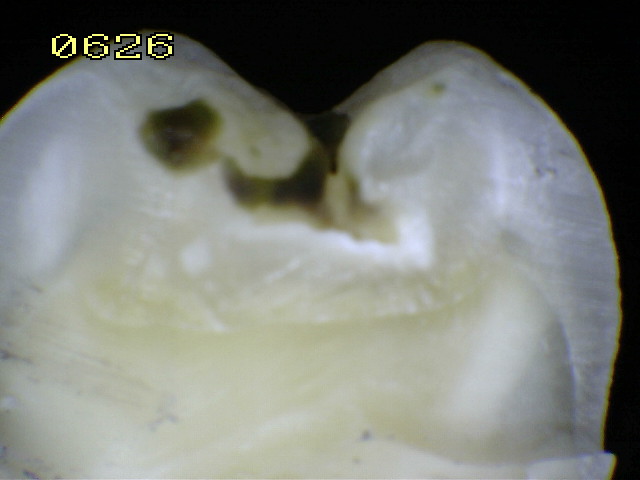

Espécimen Nº 28 |

|

| Corte sagital A:

Observe como el corte en la fosa presenta caries en dentina,

compatible con un código 2 histológico |

Corte sagital B: En la fisura es un

código 2 histológico |

Espécimen Nº

41 |

Código histológico 1 |